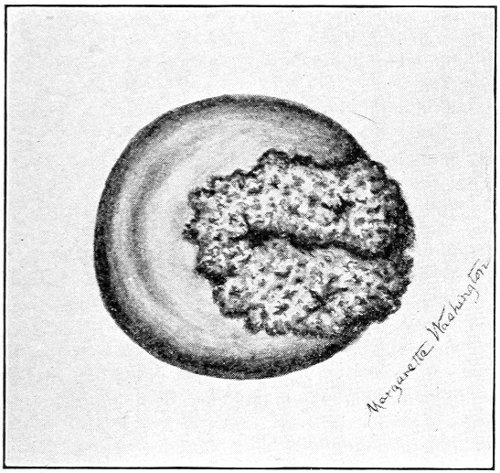

Suppuration of the vulvo-vaginal gland is accompanied by marked swelling and peripheral edema. The swelling may extend to the anus, and is of characteristic shape (Fig. 17). The pain is always severe. Fluctuation is first apparent on the inner surface of the labium majus. If the condition is not treated, one or more fistulous openings appear below the orifice of the duct, and the pus is discharged. The condition then becomes chronic. The fistulous openings persist. Acute inflammation disappears from the gland, leaving it in a condition of hypertrophic induration. A thin, milky or greenish, purulent fluid may be pressed out of the duct or the fistulous openings. Infection from this discharge may be communicated to man, or may ascend the genital 40 tract, producing inflammation of the endometrium or of the Fallopian tubes.

Fig. 17.—Abscess of right vulvo-vaginal gland.